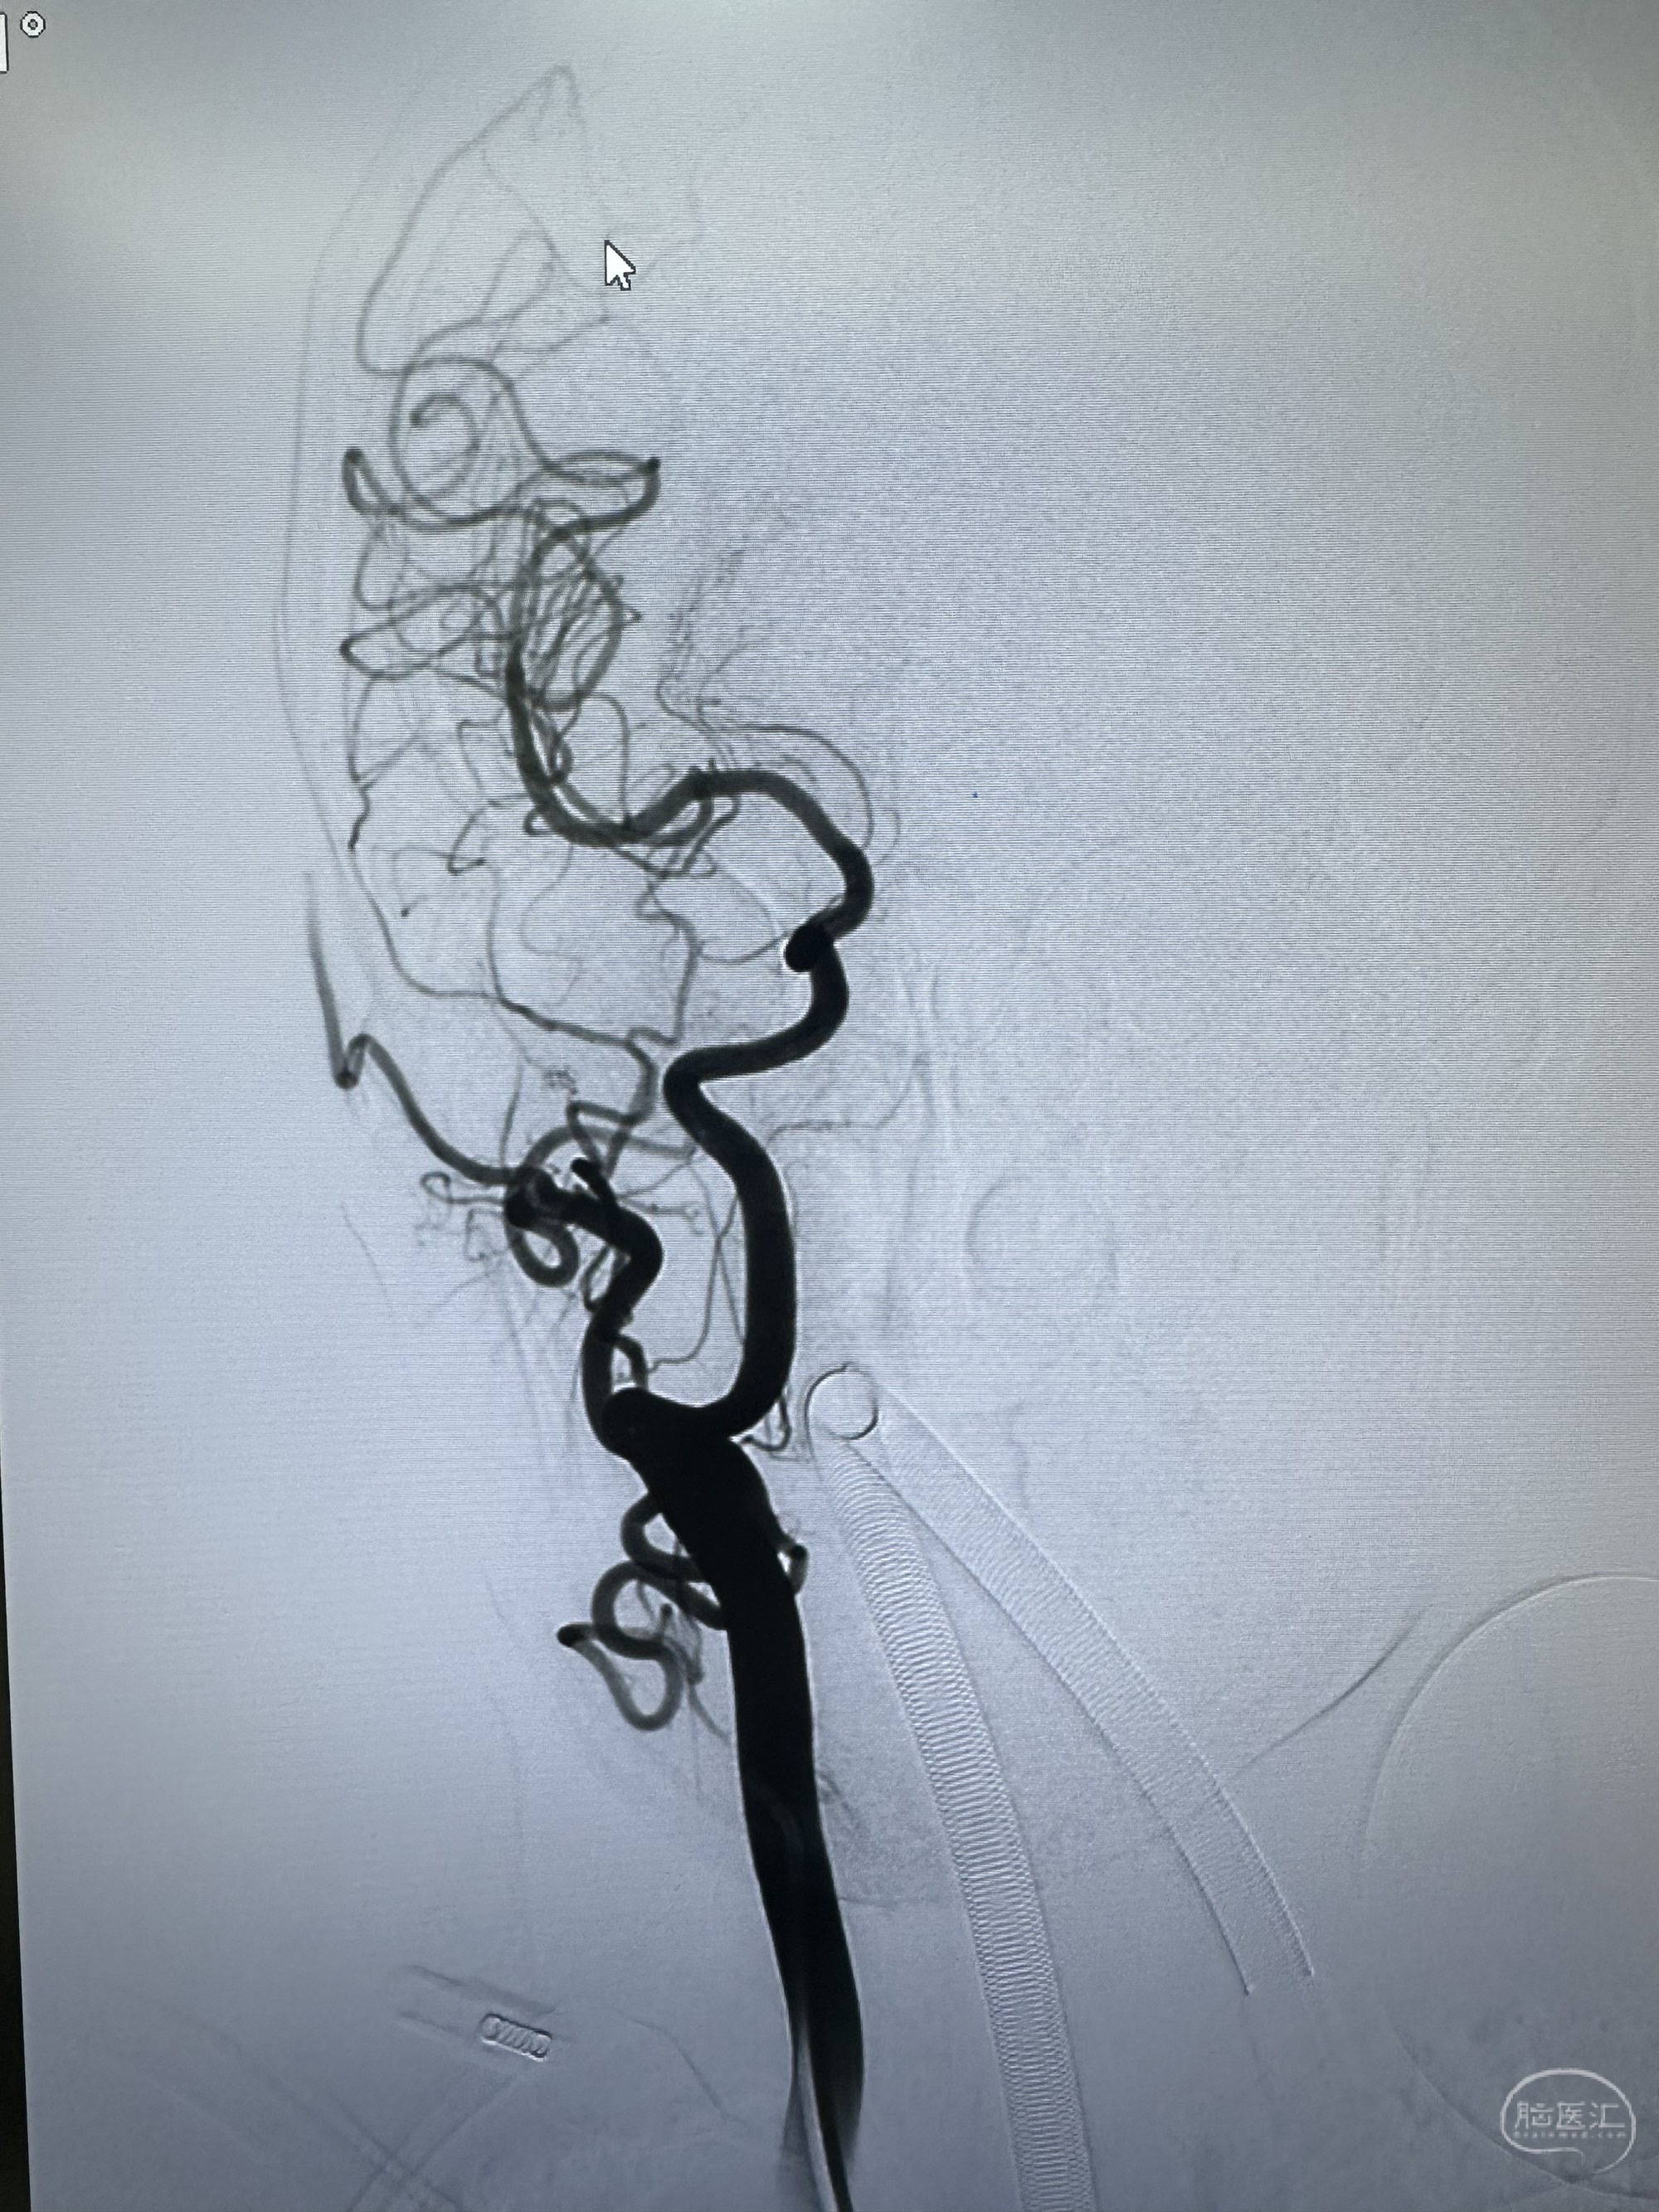

左侧造影

侧位